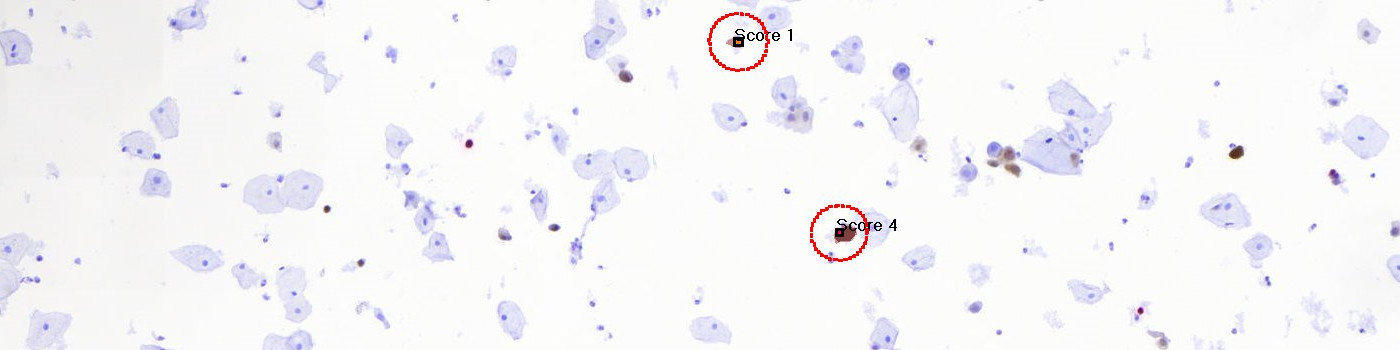

The APP detects and scores the dual stained p16/Ki-67 cells. The detection and scoring of dual stained p16/Ki67 objects is based on the calculation of p16 (DAB), Ki-67 (Fast Red) and Hematoxylin color-deconvolution bands. These bands are used as the input parameters to a naive Bayesian probabilistic classifier identifying positively stained nuclei, and unsurely or positively stained cytoplasm. Objects are defined by connected regions of red pixels, restricted by the 4-pixel connectivity rule, with a profile area corresponding to a typical relevant nucleus. In the protocol, the scoring of the detected object nucleus is solely based on the characteristics of the cytoplasm that surrounds the detected red nucleus, in the following way (see FIGURE 3):

– 0 (red nucleus without positive or unsure cytoplasm),

– 1 (red nucleus with unsure cytoplasm),

– 2-3 (red nucleus with positive and unsure cytoplasm) and

– 4 (red nucleus with positive cytoplasm).

Detected nuclei and cytoplasm, of either of the scored detections, in close conjunction are defined as larger clusters and handled separately.